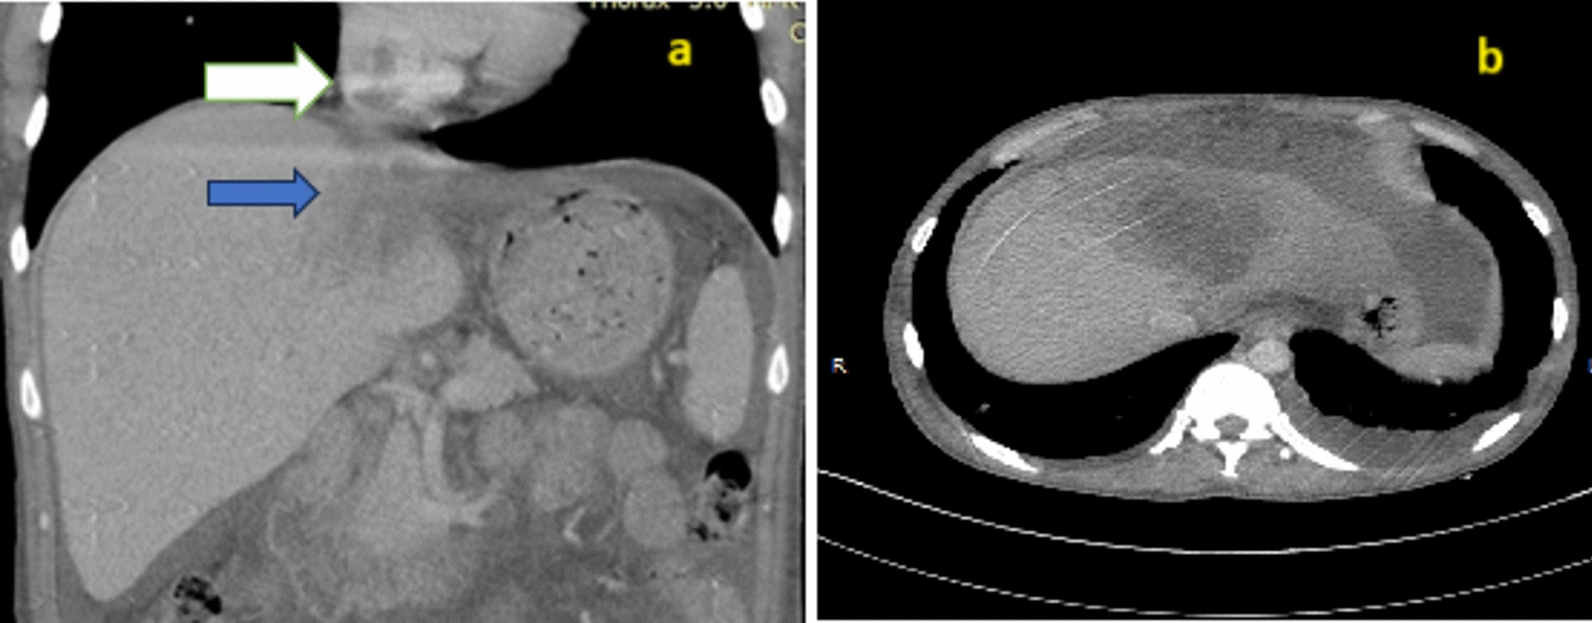

Case presentation: A 45-year-old Indian male presented with multiple episodes of fever with chills, palpitations, dyspnea, right upper abdominal pain, bilateral lower limb edema, and petechia for 20 days. On examination, tachycardia, tender hepatomegaly, and reduced air entry in the right lower lobe of the lung were observed. Ultrasound revealed an abscess in the left lobe of the liver about 150 cc in volume, abutting the inferior vena cava with rupture into it. Contrast-enhanced computed tomography imaging showed 5.7 × 6.2 × 5.4 cm segment IV A liver abscess with capsule breach into the intrahepatic vena cava and thrombus extending up to the right atrium was observed. Computed tomography-pulmonary angiography revealed a right atrium thrombus with bilateral pulmonary artery thrombus and parenchymal infarcts. Raised D-dimer, protein C and S deficiency was observed. The patient was managed by needle aspiration of abscess, anticoagulation, and antibiotics.